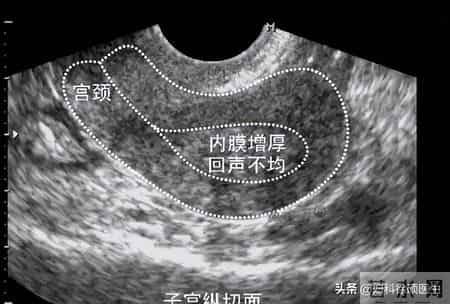

举个例子:小李的案例。她32岁,内膜一直偏厚,B超显示“不均质回声”。我问她:“最近是不是总熬夜?”她愣住:“医生,你怎么知道?我确实最近工作忙,天天凌晨睡……”长期熬夜会扰乱下丘脑-垂体-卵巢轴,让雌激素“失控”,内膜自然“疯长”。